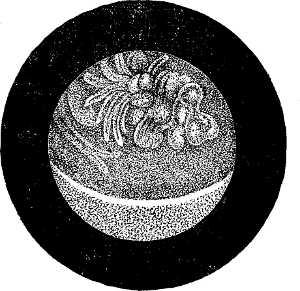

| XII. SURGERY.—Papillomatous Tumor of the Bladder, demonstrated by Means of Lister's Electro-cystoscope.—By F. N. Otis, M.D.—An interesting instance of the use of an exploratory electric light.—2 illustrations. | 10354 |

| Tumors of the Bladder Diagnosed by Means of the Electro-Endoscopic Cystoscope.—By Dr. Max Nitze.—The same general subject in further detail, giving the German practice.—5 illustrations. | 10353 |